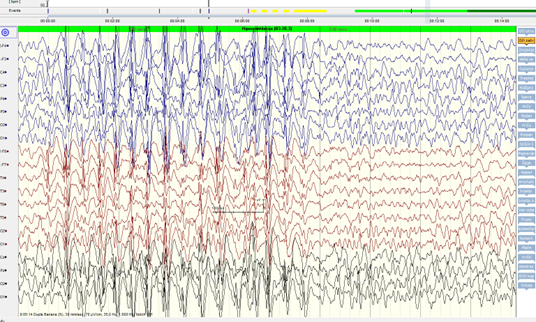

Generalizirane epilepsije obično imaju karakteristične promjene u interiktalnom EEG-u koje karakteriziraju uglavnom paroksizmalna izbijanja šiljak val kompleksa frekvencije 2-4 Hz do 120 uV. (slika 1,2).

Iktalni zapis u EEG-u je obično remećen mišićnim artefaktima. Ponekad u toničkoj fazi napadaja u sklopu generalizirane epilepsije možemo vidjeti periode izravnjivanja električne aktivnosti u EEG-u ili sniženja voltaže uz ubrzanje frekvencije, nakon koje slijedi povećanje amplitude (voltaže) uz snižavanje frekvencije. Nakon toga dolazi do postupnog izbijanja visokovoltažnih sporih poli-šiljak i šiljak val kompleksa s padom frekvencije do 1 Hz.

Postiktalno imamo difuzno supresiju cerebralna aktivnosti (engleski flatening), uz povremena izbijanja po tipu „burst suppresion“ ili trifazičnih valova. Navedeni period traje od nekoliko sekundi do par minuta. Nakon toga još jedno vrijeme možemo imati generalizirana ili žarišna izbijanja više voltažnih sporih valova 2-3 Hz do 100 uV.

Apsans napadaji su karakterizirani obično tipičnim EEG obrascem paroksizmalnih izbijanja šiljak val kompleksa 3-4 Hz trajanja od 3-30 sekundi (slika 3).

Pozadinska interiktalna aktivnost je obično uredna, a povremeno se mogu javljati paroksizmalna izbijanja šiljak, šiljak val i polišiljak val kompleksa.

Jedna od EEG karakteristika napadaja u sklopu generaliziranih epilepsija su i učestalija javljanja paroksizmalnih izbijanja na metode provokacije, poglavito na fotostimulaciju. Deprivacija spavanja ponekad može dovesti do učestalijeg javljanja paroksizmalnih izbijanja, pa se ponekad EEG snimanje planira nakon deprivacije spavanja, poglavito u djece.